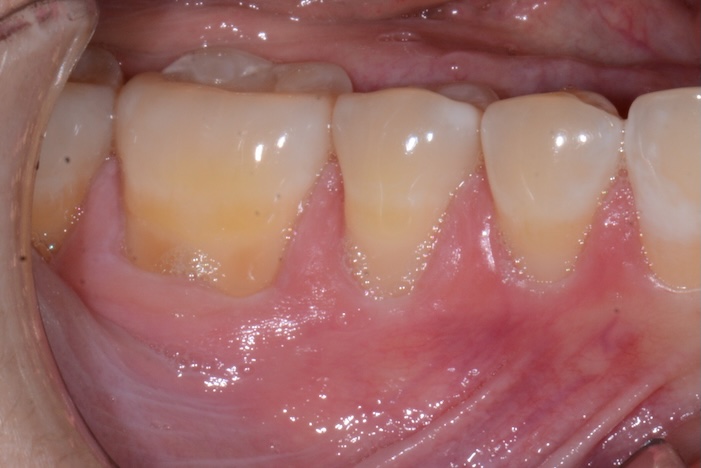

Kim was afraid to have her receding gum line fixed. Dr. Martin used a minimally-invasive gum grafting technique to renew her smile.

A big concern for your oral health, functionality, and appearance, is receding gums. To restore your smile, we use gum grafts. This process works by using graft tissue to cover the exposed roots, protecting your smile.

Gum grafts can be a cosmetic solution but are also a common treatment after periodontal disease. They take the longest to heal from but are one of the more versatile treatments after suffering from gum loss.